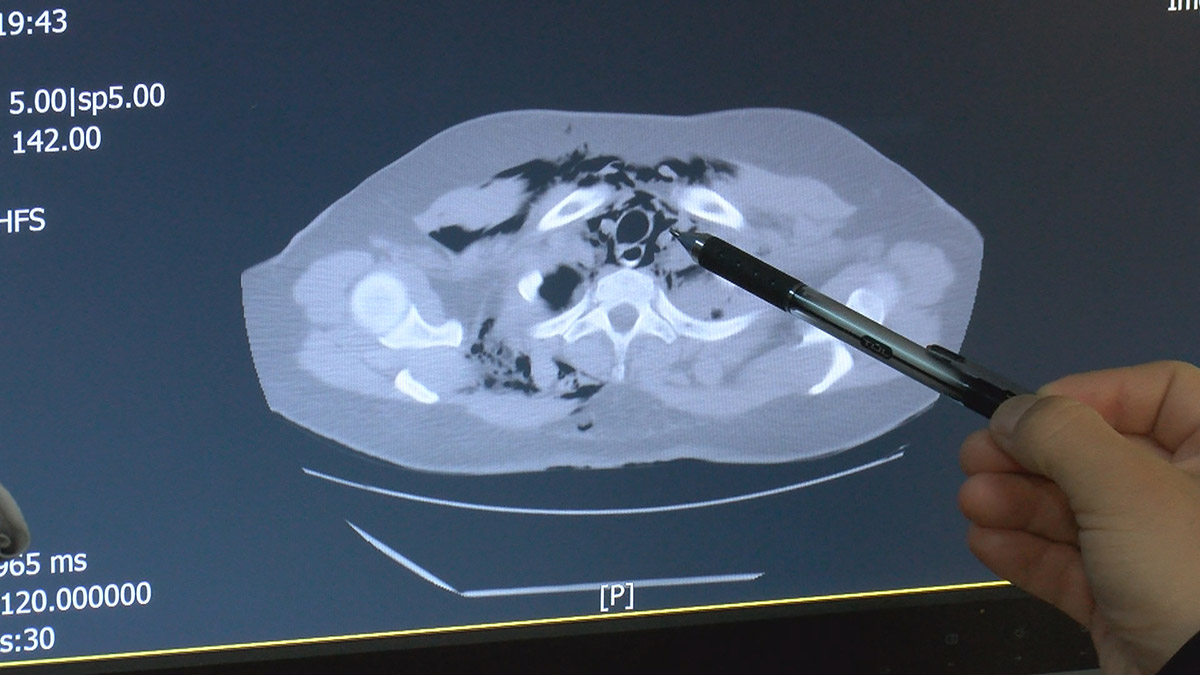

Aynı zamanda reflünün şiddetli ataklarıyla karışabiliyor. Hastanın da farkındalığı olmadığında, sağlık merkezine geç başvuruluyor. Bu hastalık başladığında hızlı bir şekilde kötüleşir. Hızla ateş yükselir, tansiyon düşüklüğü, bayılmaya kadar giden ciddi sonuçlara varabilir. Tanı koydurabilecek en ayırıcı semptomlardan biri, hastaların cilt altlarında hava kabarcıkları oluşmasıdır. Eğer boyunda ve üst göğüs bölgesinde cilt altında ele gelen hava kabarcıkları varsa hasta hemen bir acile başvurmalıdır. Teşhis için ise en önemli aracımız tomografi. Baryumlu pasaj grafisi dediğimiz yöntemle kesin tanıyı koyabiliyoruz.” diye konuştu.